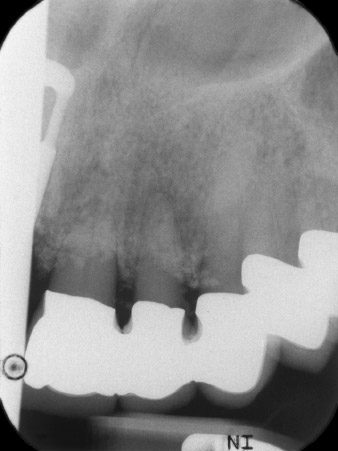

En la primera visita se trataron las piezas 21, 22 y 23, que presentaban bloqueo en las coronas colocadas hacía 19 años. Estas estaban unidas mediante una férula con los implantes de las posiciones 12/11 (figura 2). La imagen radiológica muestra una pérdida ósea horizontal alrededor de las piezas dentales 21 y 22 (figura 1).

Después de la cicatrización primaria, los tejidos blandos se modelaron con ayuda del puente con base reconstruida. Dos meses después, se procedió a la exposición del área con una incisión de la cresta maxilar en sentido ligeramente palatino (figura 2).

El hueso alveolar de la posición 22 resultó tener unas dimensiones suficientes. Las figuras 2 y 4 muestran la preparación del lecho del implante, el corte de rosca y la colocación del implante con el equipo Implantmed.